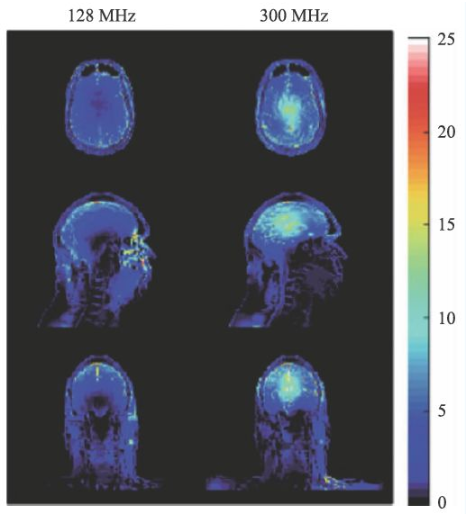

超高場(chǎng)MRI的射頻場(chǎng)設(shè)計(jì)也是一個(gè)較為困難的問題。由于射頻頻率超過了300 MHz,介電常數(shù)引起的問題非常突出。圖13 是一個(gè)在7 T 下的成像結(jié)果,可以看到在圖像內(nèi)部的信號(hào)非常不均勻,由于射頻波長(zhǎng)的極度縮短,組織的介電常數(shù)對(duì)射頻場(chǎng)的分布有極大的影響,這也是目前超高場(chǎng)MRI 需要解決的重要問題之一。目前的9.4 T以上的MRI設(shè)備還難以獲得人體體部掃描的良好圖像,其主要應(yīng)用還是做頭部的掃描。

image.png

圖13 超高場(chǎng)下的射頻場(chǎng)不均勻性

圖14 是一個(gè)SAR值對(duì)大腦溫度升高的一個(gè)仿真結(jié)果[14],對(duì)于平均SAR=3 W/kg的頭部掃描,7 T(右側(cè))下的溫度升高顯著高于3 T(左側(cè))。因此在超高M(jìn)RI中均需要配置一個(gè)可靠的SAR值監(jiān)控裝置。

圖14 局部SAR值的仿真結(jié)果